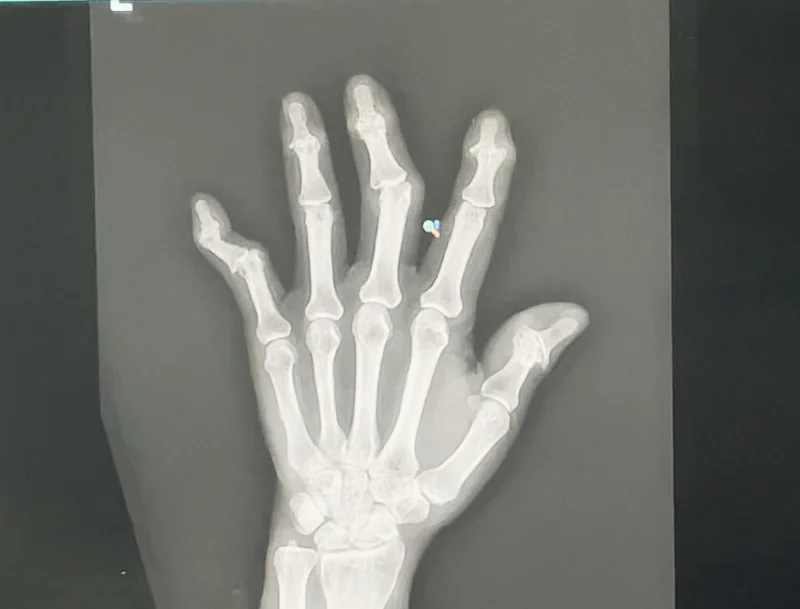

手術を行う前、X-rayを撮って確認したところ

指の関節が完全に壊れていました。

上の写真は他の患者様のケースです。今年の2月に

指の人工関節手術を受けた方です。

指の退行性関節炎で指関節の痛みが酷く

当院の噂を聞きつけて、お越しいただきました。